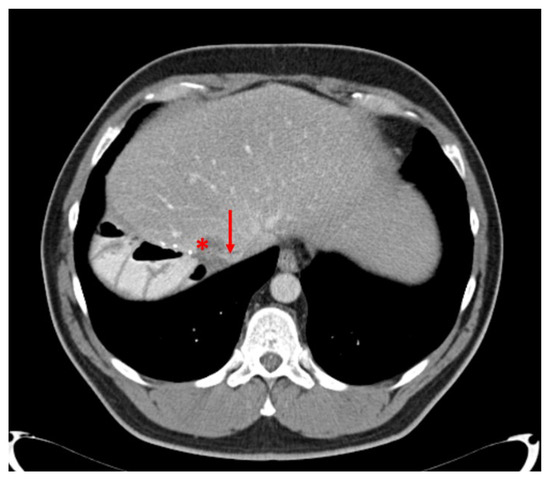

3.6. Case Report 1

The 50-year-old woman was referred to our hepatobiliary institution with synchronous bilateral CRLM in March 2011. The primary tumor (cancer of the colon sigmoideum) was resected in September 2010 at the initial point of diagnosis. She then received systemic chemotherapy with 5-FU, Oxaliplatin, Irinotecan and Bevacizumab for 3 months. The liver metastases involved the segments IVa/b, V, VII, VIII and I as well as II and III. Additionally, the CT-scan suspected an infiltration of the vena cava inferior (Figure 3). Based on the preoperative findings, an extended right hepatectomy with a resection/reconstruction of the VCI needed to be performed but the volume of segment II and III amounted only 315 mL. To avoid postoperative liver failure (PHLF) due to a too small future liver remnant (FLR) we planned an ALPPS procedure (associating liver partition and portal vein ligation for staged hepatectomy).

Figure 3. Preoperative CT-scan with a CRLM involving the VCI (Case report 1).